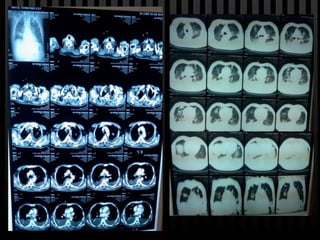

Rx de torax

28/Nov

29 – 6 pm   30   01   03

29